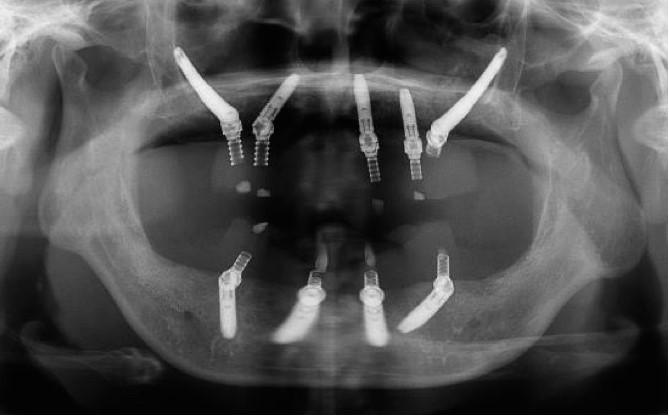

手術(shù)當(dāng)天,江宏兵院長在數(shù)字化外科導(dǎo)板和數(shù)字化導(dǎo)航輔助下,于上頜后牙區(qū)成功植入2枚Nobel穿顴種植體,前牙區(qū)植入3枚NobelParallel CC種植體,并在上頜竇開窗區(qū)及過薄的種植體唇側(cè)充填骨粉,覆蓋膠原膜。下頜則在數(shù)字化外科導(dǎo)板引導(dǎo)下,避開患者數(shù)年前充填的美容假體和其他重要解剖結(jié)構(gòu),植入4枚NobelParallel CC種植體,所有種植體初期穩(wěn)定性均達(dá)到35 N?cm,符合負(fù)重的要求。

按照術(shù)前計(jì)劃于上下頜植入共9枚種植體